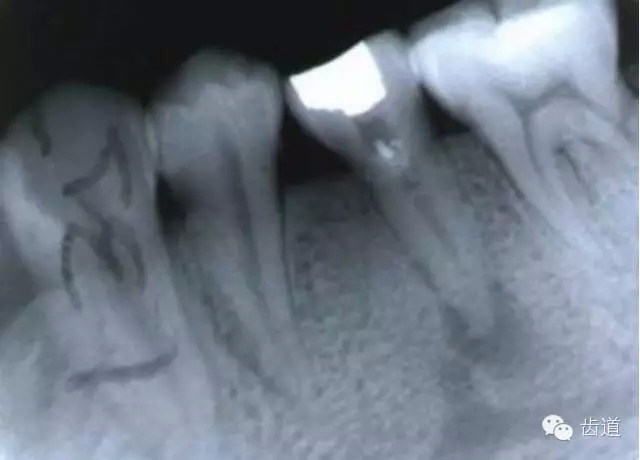

左上5牙頸部側(cè)穿

開(kāi)髓時(shí)鉆針進(jìn)入方向與根管走行方向不一致,鉆針需改變方向時(shí)。

牙長(zhǎng)軸傾斜,在傾斜方向的髓腔壁易穿孔

左下6底穿

左上6底穿

根管壁穿孔多在根管彎曲處。